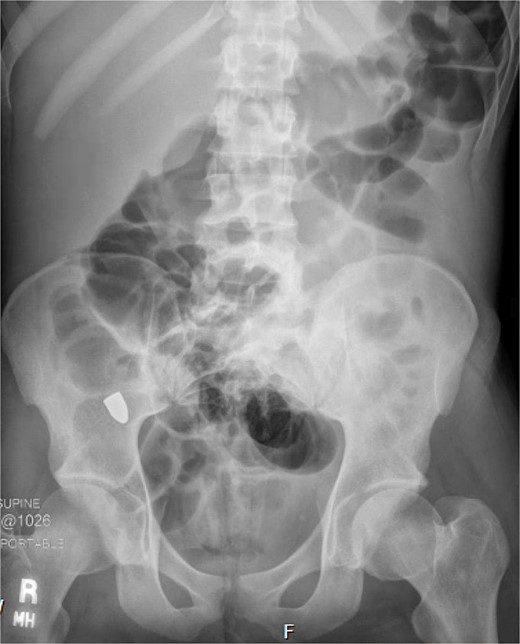

On hospital day (HD) 1, he developed ARDS and required intubation. He became hypotensive, raising concern for mediastinitis, but repeat imaging showed no new findings except that the bullet had migrated below the diaphragm (Fig. 3). Despite his septic appearance, his condition didn’t improve. He was diagnosed with severe AIDS (CD-4 count <100 cells/mm3) and multiple infections (hepatitis A, C, cytomegalovirus, toxoplasmosis, and multi-drug-resistant Pseudomonas pneumonia).

A repeat otolaryngology endoscopy exam on HD 2 revealed a 1.5 cm wound in the posterior pharyngeal wall, confirming the suspicion that the bullet entered the posterior of the mouth, was swallowed, and was now migrating down the GI tract. Serial X-rays tracked its transit (Fig. 4). Despite treatment, his condition remained critical. He underwent tracheostomy, gastrostomy, and diaphragmatic pacemaker placement. The patient was discharged to a long-term care facility on HD 22 but succumbed to complications from AIDS and pneumonia months later.

A FB in the GI tract will pass naturally in most cases. Serial images can be used to monitor transit through the gut. Stools can be monitored for evacuation [4, 5]. Obstruction or perforation by any FB is possible. Concern may be raised if the object fails to progress, especially in the right lower quadrant at the cecum. Patients developing signs of bowel obstruction or peritonitis warrant exploration [12, 13].